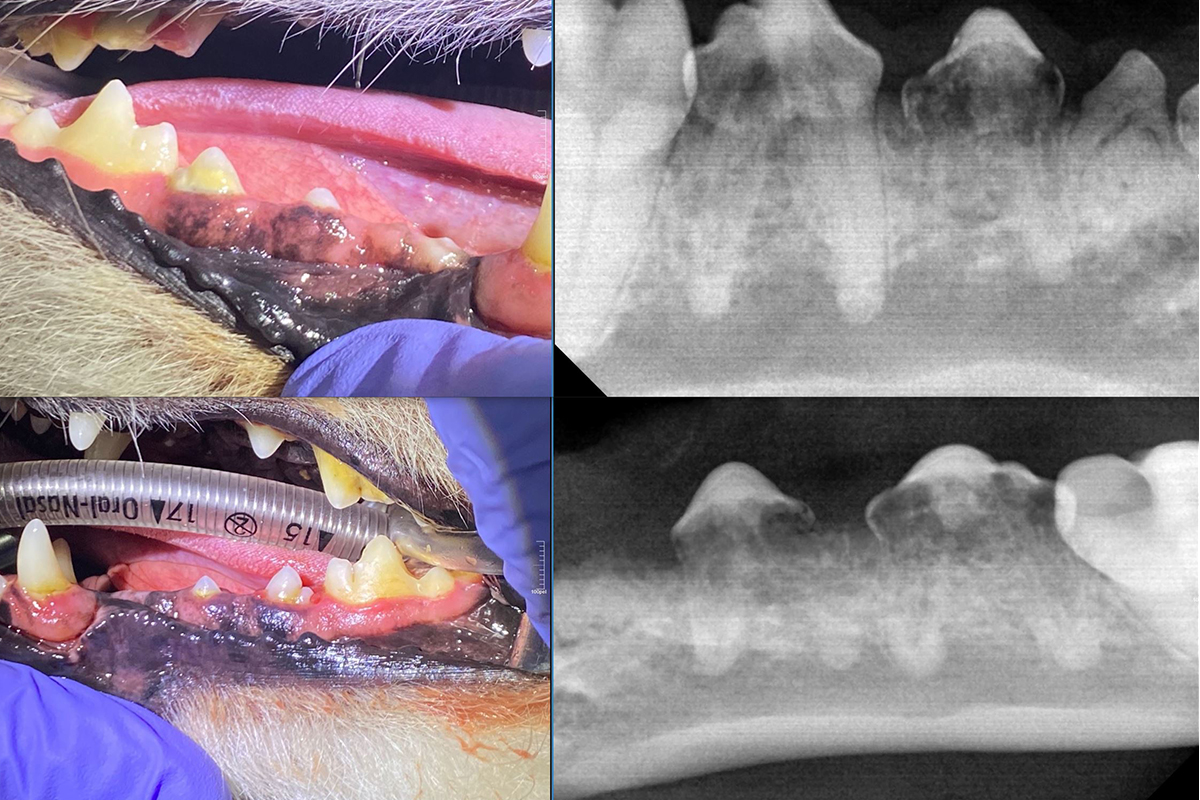

스케일링 전후 사진

스케일링 전

스케일링 후